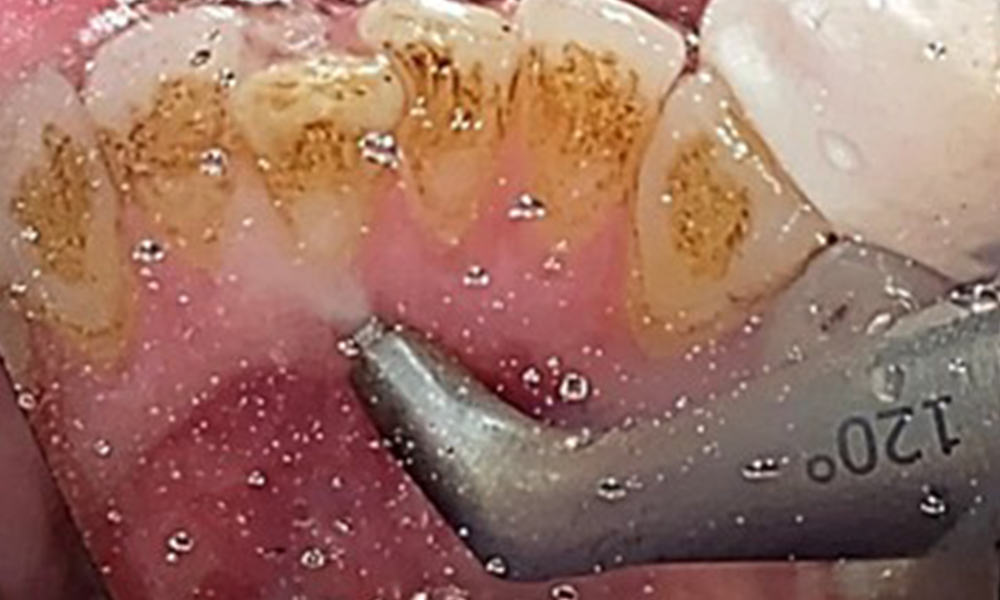

Obiectivul planului trebuie sp fie controlul riscului de boală, prin îndepărtarea biofilmului sub- și supragingival. Instrumentarul va fi ales în funcție de particularitățile pacientului. În primul rând, tartrul și eventualele concrețiuni vor fi înlăturate cu ajutorul pieselor cu ultrasunete și/sau manuale (Fig. 10).